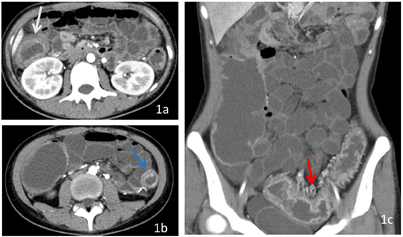

CT图像显示结肠肠壁弥漫性均匀增厚,最厚处约1.5cm,病变肠管内壁呈凹凸不平锯齿样改变,增强扫描呈明显分层强化,病变肠管管腔变细,系膜侧小血管增多、增粗、迂曲。患者随后进行了肠镜和病理活检,病理结果显示为溃疡性结肠炎。临床诊断为慢性复发型全结肠型重度溃疡性结肠炎活动期。给予对症治疗和美沙拉嗪抑制免疫治疗,病情好转。

UC是一种非特异性慢性炎症性肠病,病因不明,易复发。诊断主要基于临床症状、实验室结果、内镜及组织学评估[1]。由于内镜是侵入性检查,部分患者无法忍受,且内镜检查无法观察肠外情况[2]。且对于不同分级、分期、病变部位的患者采用不同的治疗方法,准确诊断疾病对治疗及预后至关重要[3]。CTE可作为内镜检查的辅助检查手段,用于评估病变范围、分布、严重程度、病情分期、肠外情况及并发症[4]。CTE是采用双能量进行扫描,检查前患者饮用大量水,将肠腔充盈,有利于显示肠壁及腔内情况,在140kV下采集的CT图像较80KeV对比度增强,两者的融合图像对病变显示最佳(图1,图2)。同样的数据可用于进行MIP和CR后处理,不增加患者的辐射剂量,在MIP图像上,能够显示病变肠管周围的肠系膜血管,对"齿梳征"的显示更加清楚;在CR图像上能显示UC特有的"舞龙征"[5],有助于UC的诊断。骨结构可以通过syngo.CT Direct Angio去除,以清晰显示血管和病变肠管(图4b)。所有这些应用程序都是在自动化的工作流中执行的。